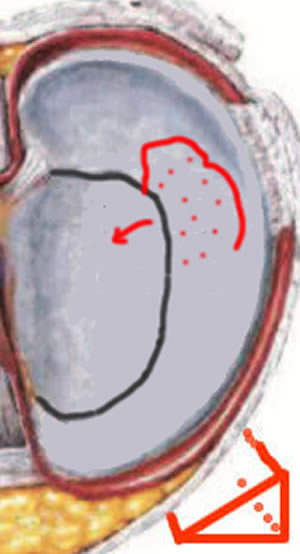

Fissure traumatique avec languette

Ici, la fissure est transfixiante, complète et libère une languette; vue du dessus